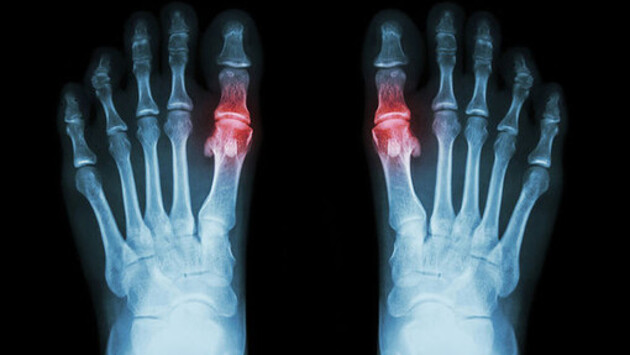

Исследователи из Ноттингемского университета вместе с коллегами из Кильского университета (Великобритания) обнаружили, что риск сердечного приступа и инсульта временно увеличивается в течение четырех месяцев после обострения подагры. Результаты опубликованы в журнале JAMA. Команда использовала медицинские данные 62 574 пациентов с подагрой, содержащиеся в Национальной службе здравоохранения Великобритании. Ученые обнаружили, что у многих пациентов с подагрой, перенесших сердечный приступ или инсульт, часто наблюдался приступ подагры за 60 дней до приступа. У пациентов с подагрой, которые умерли из-за инфаркта или инсульта, вероятность наличия приступа подагры в предшествующие 60-120 дней в 2-4 раза выше, чем у остальных пациентов. Это исследование показаывает важность длительной терапии пациентов с подагрой препаратами на основе аллопуринола, противовоспалительными лекарствами и соблюдения специальной диеты. Подагра — это распространенная форма артрита, которая вызывается высоким уровнем мочевой кислоты, откладывающейся в суставах и вокруг них в виде игольчатых кристаллов. Их разрушение приводит к сильному воспалению в течение 1-2 недель, которое сопровождается сильным отеком, покраснением и болезненностью. От подагры страдает 1 из 40 взрослых людей в Великобритании.